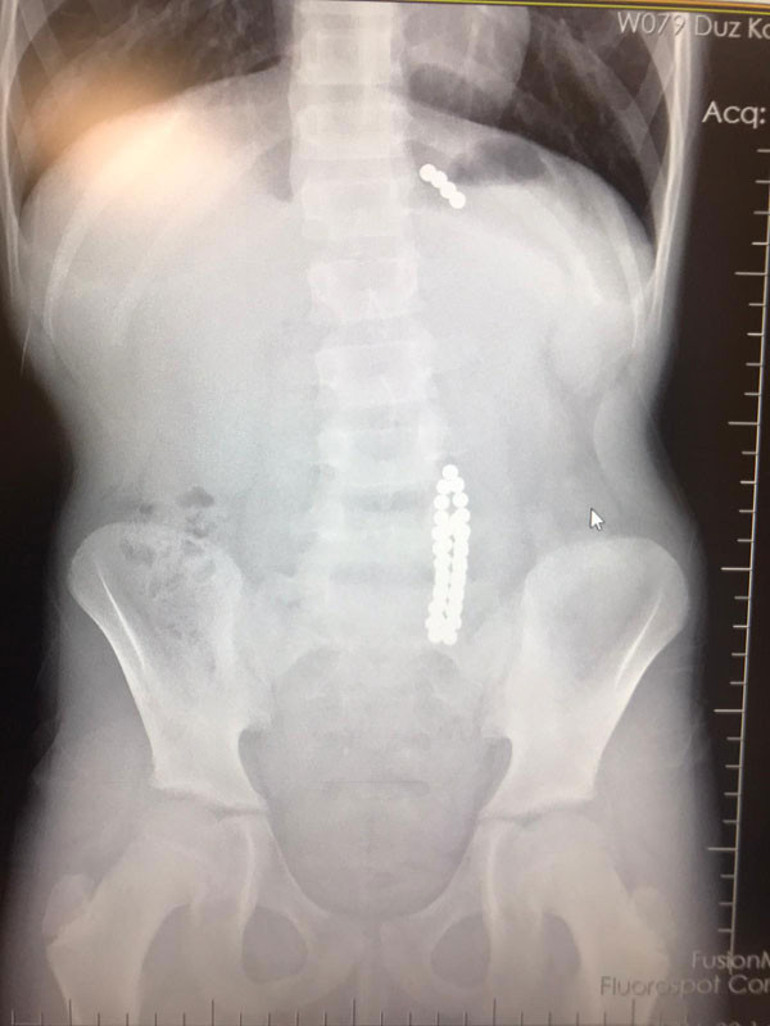

Beylikdüzü’nde 9 yaşındaki bir çocuk ailesinin haberi olmadan neodyum adı verilen stres bilyeleri olarak da bilinen 42 adet mıknatısı yuttu. Birkaç gün sonra şiddetli karın ağrısı ve kusma şikayeti ile hastaneye gelen çocuğun röntgeni çekildi. Röntgen filminde çocuğun midesinde boncuklar halinde yabancı bir cisim tespit edildi. Bağırsağını delen cismi fark eden Beykent Üniversitesi Çocuk Cerrahisi Uzmanı Prof. Dr. Ali Çay çocuğu ameliyata aldı. Yapılan ameliyatta çocuğun bağırsaklarından rengarenk şekilde 42 adet neodyum çıkarıldı.

Prof. Dr. Ali Çay, “42 adet neodyum mıknatıs yutan 9 yaşındaki bir hastada buna bağlı bağırsak yırtılması meydana geldi. 8 gün farklı hastanelerde tedavi olmak için bekleyen hasta 1 saatlik operasyonun ardından mıknatıslardan kurtuldu. Çoklu mıknatısların yutulması durumunda mıknatıslar bağırsak içerisinde birbirine yapıştığı için, iki bağırsak segmentini birbirine yapıştırıyor ve bağırsakta delinmelere sebep olabiliyor” diye konuştu.